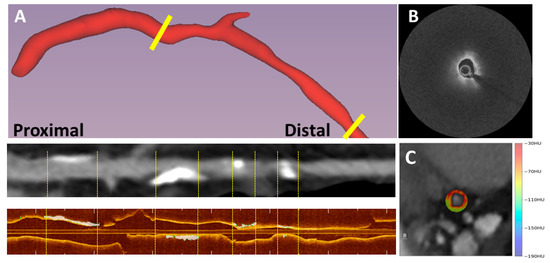

2.2. IVOCT Imaging

2.3. The Use of IVOCT Processing to Extract Vulnerability Characteristics

2.5. The PCAT Segmentation